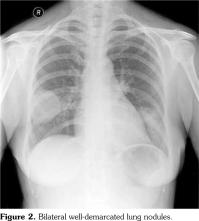

She relapsed again in 2011, whereby at that time, she presented with two weeks history of nasal blockage, epistaxis, and fever. Clinically, her nasal septum was deviated (Figure 1). The nasal cavity was inflamed, fragile, and bled to touch. Her chest X-ray revealed well-demarcated lung lesion (Figure 2). She refused biopsy of the lung nodules. Fortunately, the lung lesion disappeared with oral prednisolone 1 mg/kg body weight. She was readmitted again after four months due to a two-day history of swollen right lower limb. There were no histories of fever, shortness of breath, hemoptysis or cough with pleuritic chest pain. She was not cyanosed. Her blood pressure was 110/85 mmHg with heart rate of 80/minute and regular rhythm. Her respiratory rate was 20 per minute. Clinically, her right calf was swollen with warmth and erythema. Chest, abdominal, and neurological examinations revealed no abnormalities. There were no effusion, patch infiltrates, Westermark sign or Hampton hump. A Doppler ultrasound test of her lower limbs revealed a thrombus at right common femoral vein. Other classic risk factors for DVT were absent. Thrombophilia screening including protein C, protein S, lupus anticoagulant, anticardiolipin antibody, anti-β2 glycoprotein-I antibody, and anti-thrombin III were all normal. Subcutaneous low molecular weight heparin was initiated for the DVT. However, she had complication with methicillin-resistant Staphylococcus aureus septicemia secondary to catheter related infection during her stay in the hospital. Despite good antibiotic coverage with intravenous vancomycin, she had persistent methicillin-resistant Staphylococcus aureus septicemia and succumbed after one month of hospitalization.